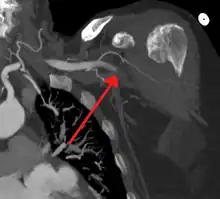

![]() | |

| Acute embolism to the right femoral artery resulting in ischemia | |